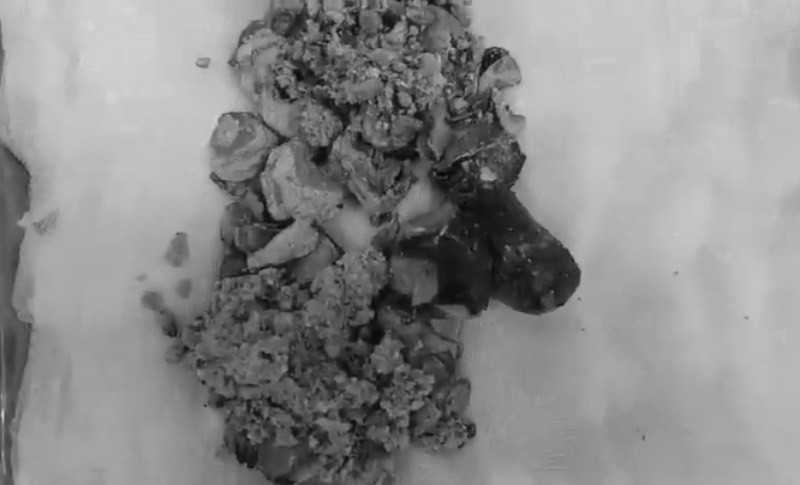

Bác sĩ đã quyết định mổ mở để lấy sỏi thận. Quá trình phẫu thuật, các bác sĩ bóc tách được viên sỏi san hô dài tới 20 cm, nặng 500 g. Bác sĩ Liên cho biết trường hợp này may mắn vì chức năng thận đã phục hồi, bệnh nhân không phải chạy thận chu kỳ. Sau 10 ngày điều trị theo dõi, sức khỏe bệnh nhân đã hồi phục và ra viện.

Sỏi khổng lồ nặng 500g đã được các bác sĩ bóc tách. Ảnh BSCC.